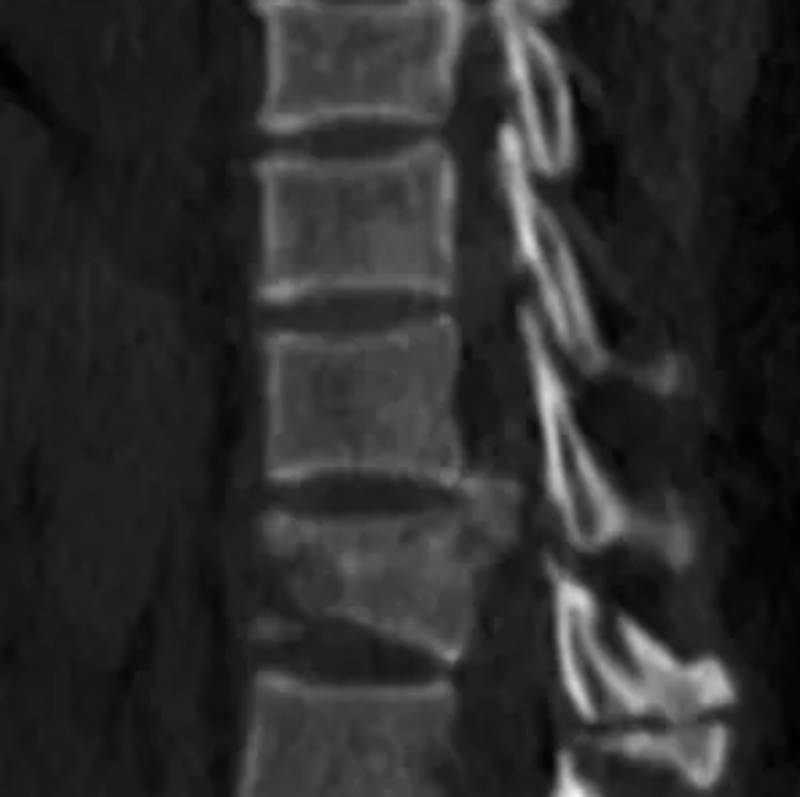

在今年4月份,42岁的韦女士因被电线杆压伤致全身多处外伤被送至我院就诊。经检查,患者双侧液气胸、双侧少量气胸、左侧胸腔少量积液(积血)、右侧胸腔中等量积液(积血)、双肺挫伤;胸4、12椎体爆裂性骨折伴骨性椎管狭窄,胸4椎体骨折分离、移位;颈7、胸1左侧横突、左侧第1-10、12肋及右侧第1-7肋骨折,颈7、胸1-4/12棘突、胸8/9左侧横突骨折;失血性休克;创伤性湿肺;失血性贫血;多器官功能损害;头皮撕脱伤;右小腿开放性骨折。因韦女士病情极其危重后收入我院重症医学科治疗。

△胸4椎体爆裂性骨折伴脱位。

胸12椎体爆裂性骨折,骨折碎块压迫椎管。